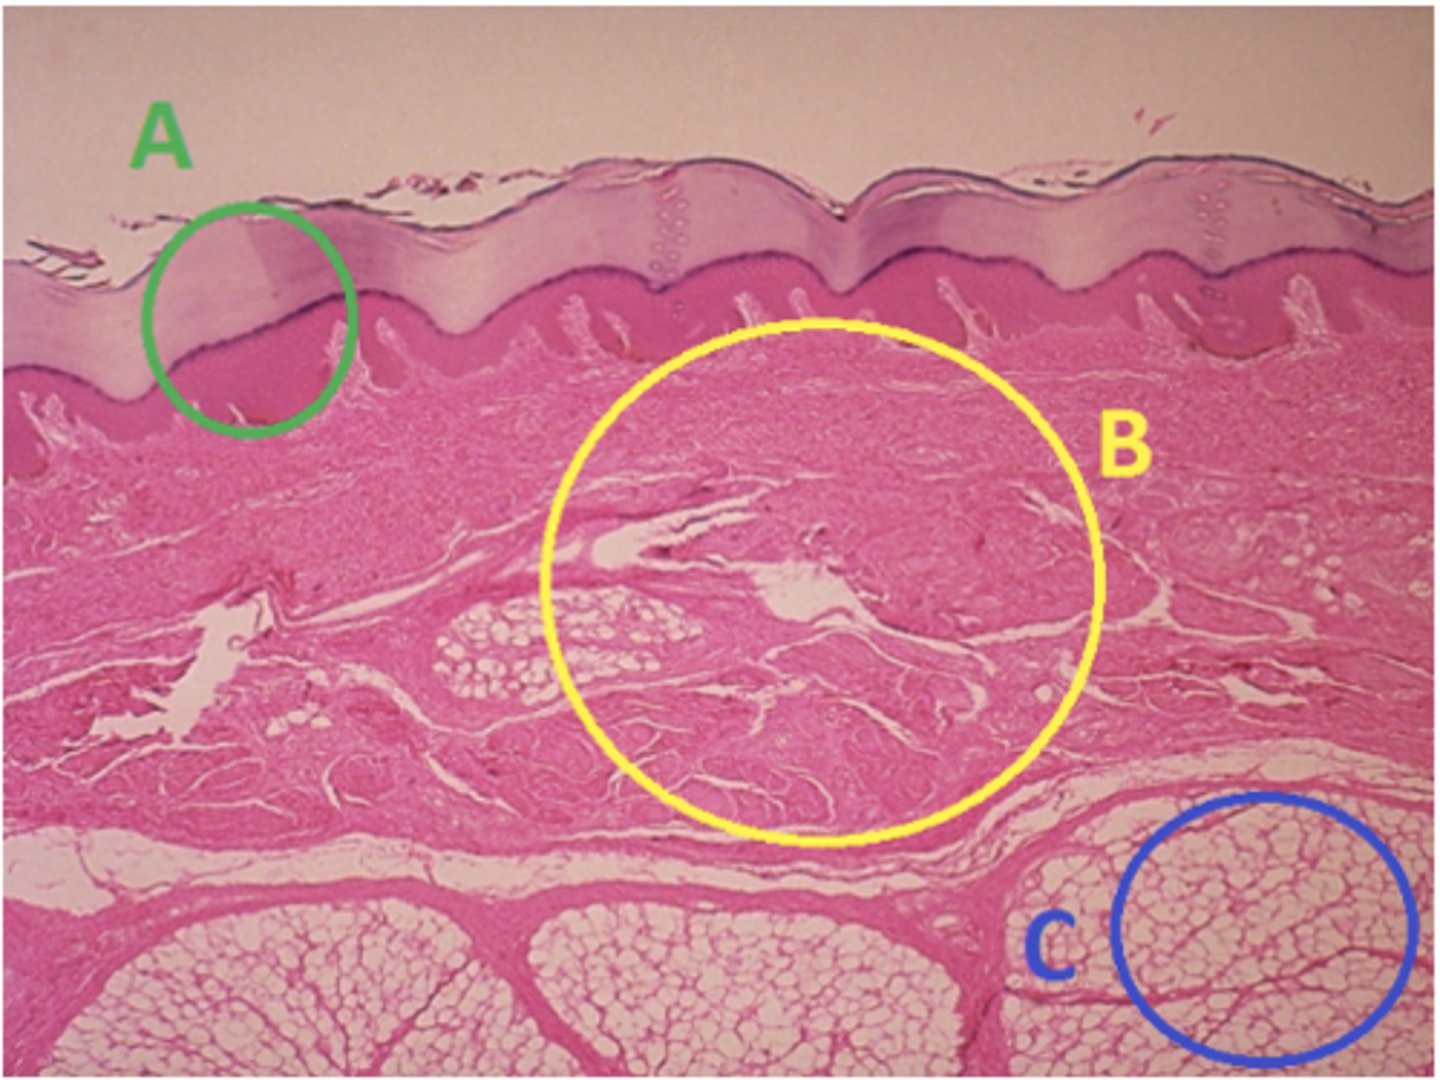

C - hypodermis

Answer the following questions based on the features indicated in the following image. Which letter indicates the administration site for subcutaneous injections?

A - epidermis

Answer the following questions based on the features indicated in the following image. Which letter indicates the administration site for topical creams and ointments?

B - Dermis

Answer the following questions based on the features indicated in the following image. Which letter indicates the administration site for the tuberculin skin test?

A - epidermis

Answer the following questions based on the features indicated in the following image. Which letter indicates a region of the skin with no nerves or blood vessels?

B - Dermis

Answer the following questions based on the features indicated in the following image. Which letter indicates the region where skin appendages (sweat glands, sebaceous glands, and hair follicles) have their roots?

Epithelial tissue

Answer the following questions based on the features indicated in the following image. Which of the four major tissue types is indicated by letter A?

Skin of the soles of the feet

Where would hair follicles be absent?

Skin in the axilla (armpit)

Skin on the back of the hand

Skin of the dorsal surface of the feet

Skin of the soles of the feet

C

Which letter indicates the administration site for insulin injections?

A

Which letter indicates the administration site for a lidocaine patch?

B

Which letter indicates the administration site for an allergy test?

B

Which letter indicates a region of the skin rich in dense, irregular connective tissue?

C

Which letter indicates the region most important for energy storage and thermal insulation?

Connective

Which of the four major tissue types is indicated by letter C?

Skin of the dorsal surface (back) of the hand

Which part of the body could the previous image represent?

Skin of the ventral surface (palm) of the hand

Skin of the dorsal surface (back) of the hand